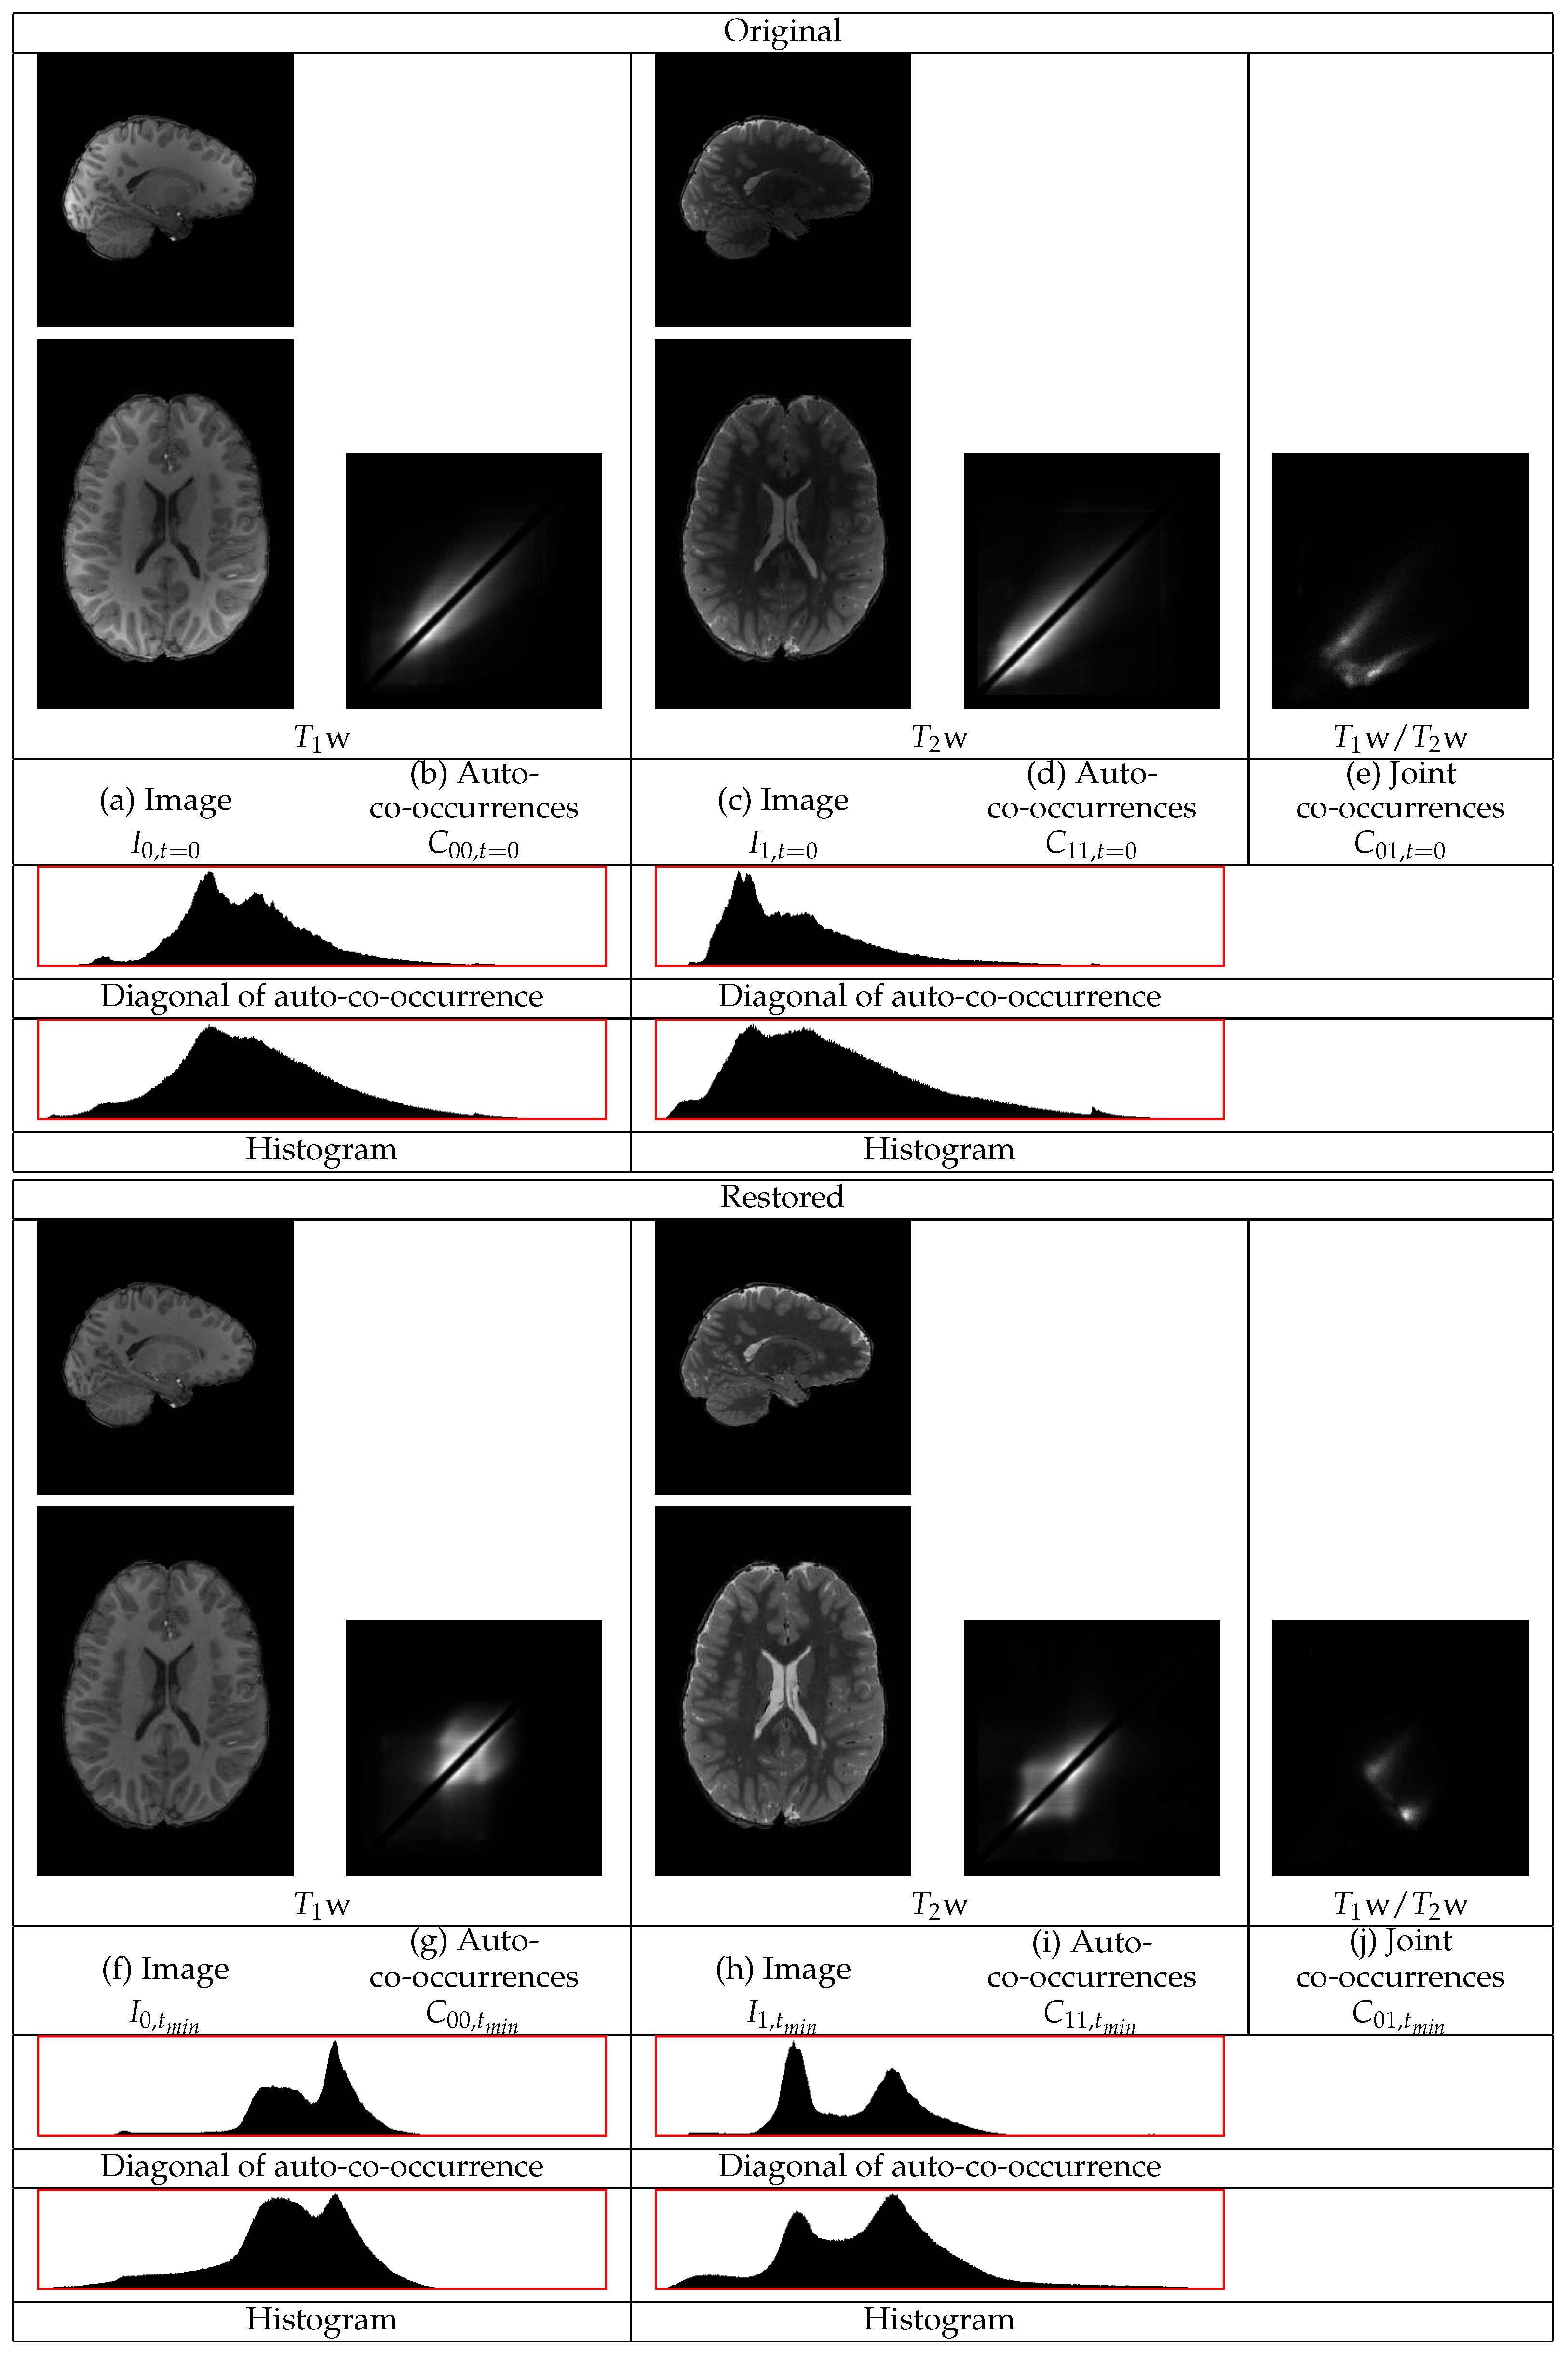

The restoration of representative w and w images of an HCP volunteer are shown in Figure 6. The GM tissues in the cortex, subcortical regions, and the cerebellum become of more uniform intensity in both images. The intensities of the WM also become more uniform. The statistics of both the w and the w images in Figure 6 show different distributions corresponding to the three tissues, even along the diagonal of the auto-co-occurrences that are minimally involved in the restoration. In the w statistics, there are separate distributions corresponding to the WM and to the GM. The distribution corresponding to the CSF appears. They also show a sharper distribution corresponding to the border between the WM and the GM. In the w image, the different distributions of the WM and of the CSF become apparent. The consideration of both images shows their successful restoration.

Figure 6.

Example restoration of a w and a w image pair for the HCP LS dataset. The intensities of the white matter and the gray matter in both the w image and in the w image become more uniform. The statistical distributions become sharper.

The statistics of the initial w image have a heavy tail at the high intensity part of the dynamic range from contributions of the GM and of the CSF. Thus, the standardization of that part of the dynamic range to a limited range results in its compression. That compression causes a shift of densities from the lower intensity range to a higher intensity range.